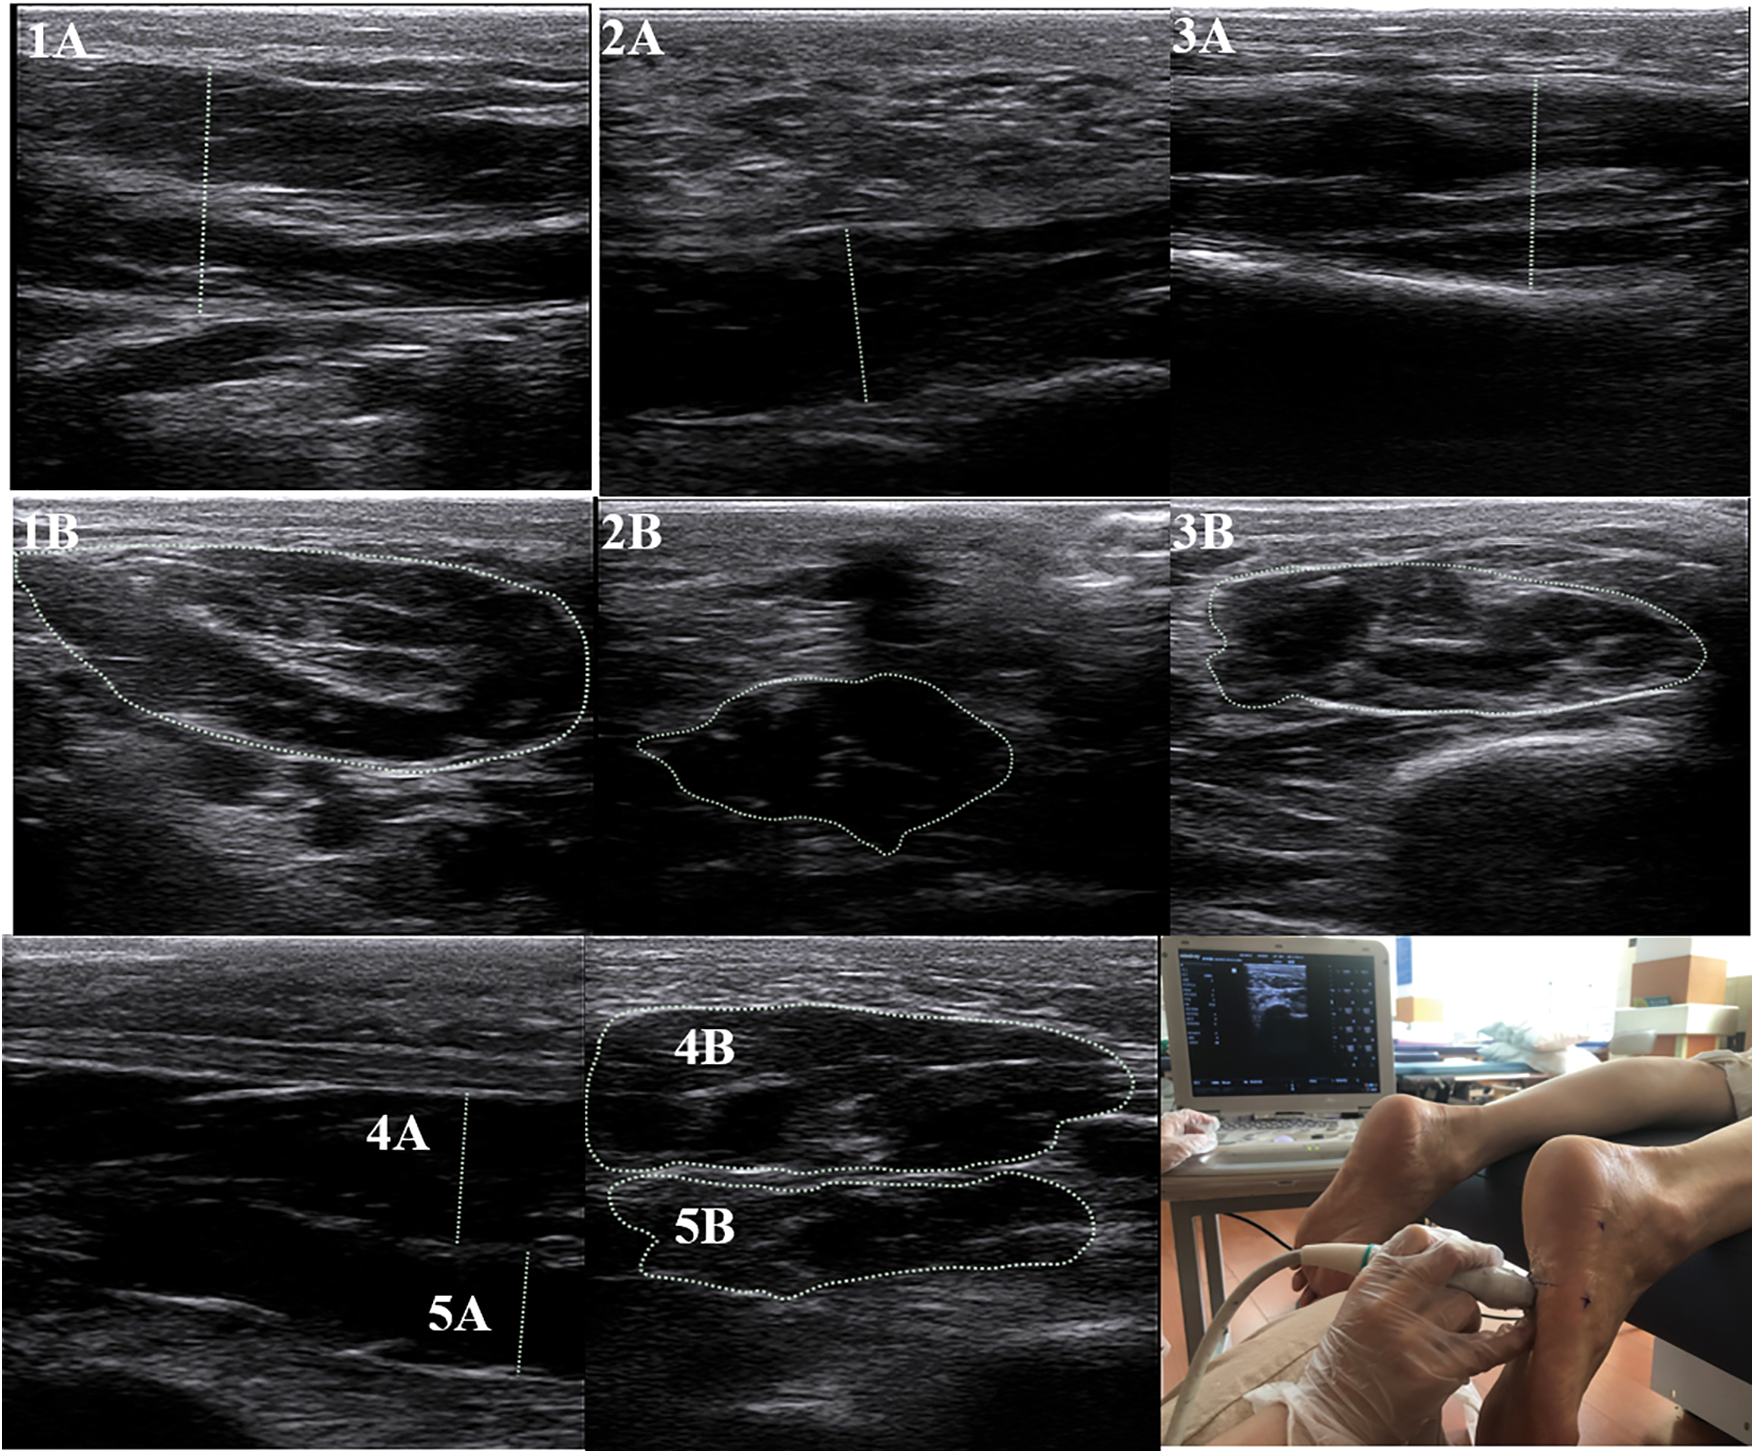

A musculoskeletal ultrasound system with a 6–14 MHz linear probe (Mindray M7, MINDRAY, Shenzhen, China) was used in measuring the muscle thickness and CSAs of the FDB, AbH, flexor hallucis brevis (FHB), QP, and abductor digiti minimi (AbDM), as shown in Fig. 2. The participants were instructed to lie down in a prone position with their ankles protruding from the bedside and drooping naturally. Muscle testing positions were determined as previously described [32]. At each measurement position, ultrasound coupling gel was applied between the skin and probe placed along the direction of a muscle fiber, and the thickness was calculated. At the thickest position of the muscle, the probe was rotated at 90° for the measurement of CSA. This method has has high intra- and inter-tester reliability [32]. After the long axis of the probe was positioned perpendicular to the muscle boundary, the image was captured when the muscle was relaxed. During the test, the ultrasound probe exerted minimal pressure on the foot sole to reduce the deformation of the tested muscle. Three images were obtained at each test location, and the probe was removed after each test.

Figure 2: Ultrasound image of foot intrinsic muscles

Note: 1 = Abductor Hallucis; 2 = Abductor Digiti Minimi; 3 = Flexor Hallucis Brevis; 4 = Flexor Digitorum Brevis; 5 = Quadratus Plantae; A = thickness; B = cross-sectional area. Due to the inconsistent anatomical shape of the muscle, some lines indicating the thickest part of the muscle may appear to be slanted.